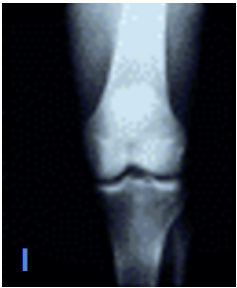

What are some of the characteristics of Kelgren and Lawrence Level I OA?

A

Minute osteophytes

Normal joint space